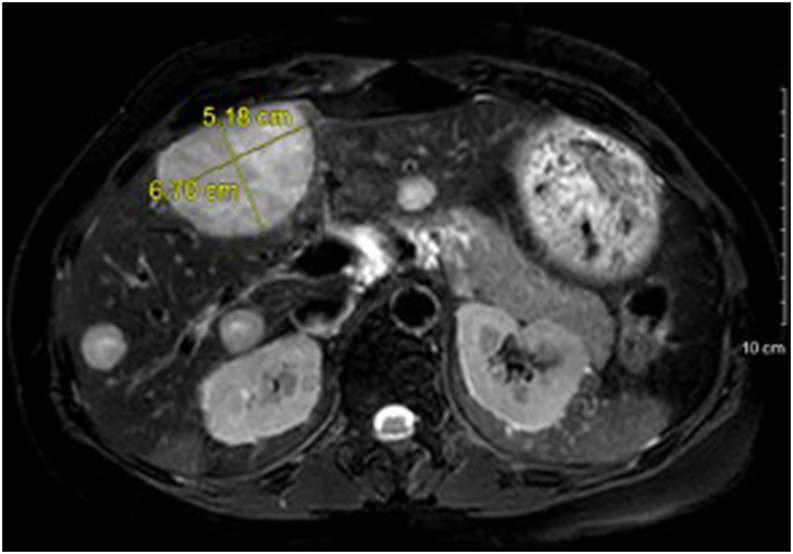

Laboratory workup after discontinuing hydrocortisone and fludrocortisone during hospitalization demonstrated undetectable ACTH with an 8 am cortisol level of 29.9 mcg/dL. Serum cortisol failed to suppress after 1-mg and 8-mg dexamethasone suppression tests. Her 24-hour urine-free cortisol and midnight salivary cortisol levels were elevated (Table). Abdominal magnetic resonance imaging revealed multiple hepatic masses (Fig. 2). There was no residual nodularity in the left adrenalectomy bed, and the right adrenal gland was unremarkable. The liver lesions were fluorodeoxyglucose avid on a positron emission tomography scan (Fig. 3), and a biopsy confirmed metastatic ACC (Fig. 4). Next-generation sequencing studies of the liver biopsy specimen revealed a frameshift loss-of-function allelic variant in the FH gene that encodes the protein fumarate hydratase (c.912_918del p.F305fs; variant allele fraction, 67.8%). Subsequently, a comprehensive panel comprising 77 genes revealed a germline allelic variant in the FH gene (c.912_918delTTTTGTC p.F305Lfs∗22).

Fig. 2.

A magnetic resonance image of the abdomen showing multiple liver lesions in a patient with metastatic adrenocortical carcinoma.